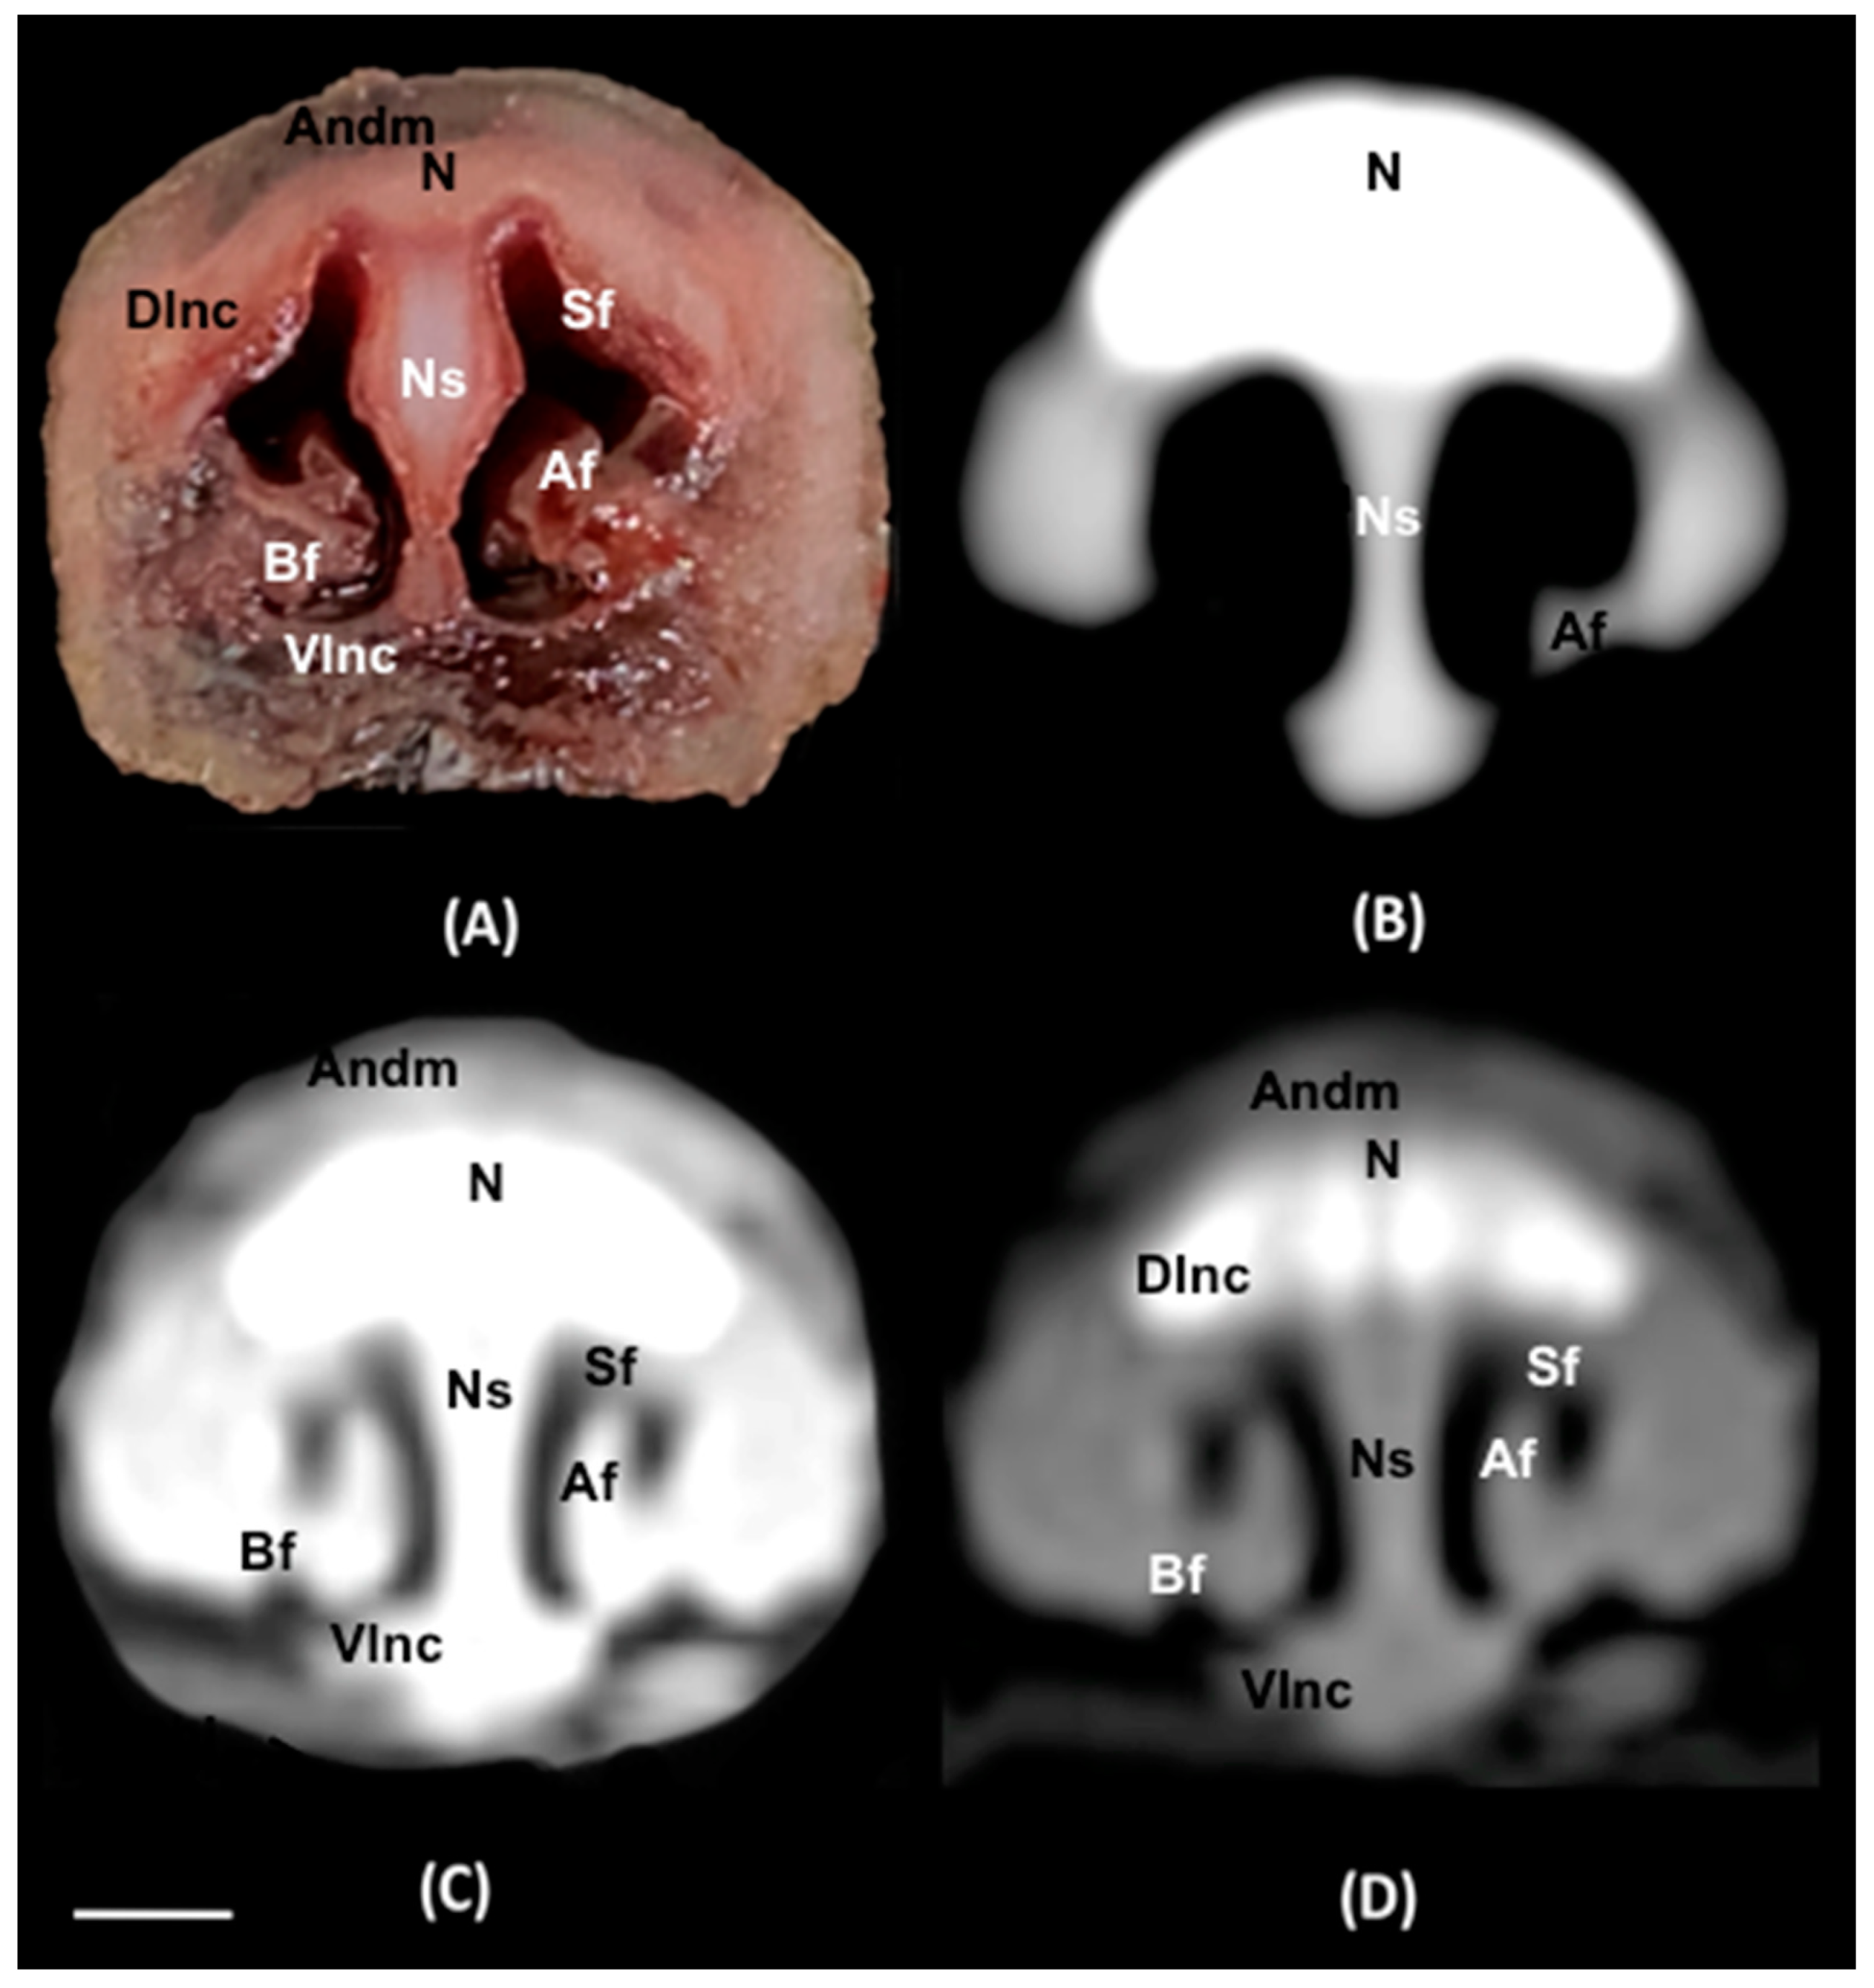

3.1. Anatomical Sections

3.2. Computed Tomography (CT)